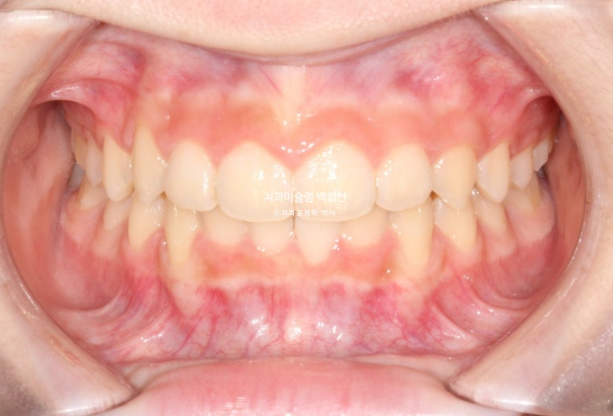

교정치료를 위해 내원한 중학생 친구입니다.

앞니 높낮이 차이가 눈에 띕니다.

가운데 앞니 두개가 내려와 토끼이처럼 보입니다.

윗니가 아랫니를 과하게 덮어 아랫니가 보이지 않을 정도입니다.

과개교합 이라고 합니다.